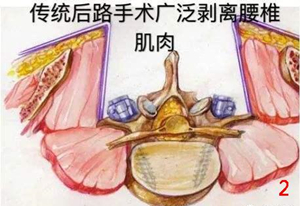

了解过腰椎退行性疾病的患者都知道,当腰椎间盘突出以及腰椎管狭窄发展到一定程度,微创孔镜下的椎管减压术已经无法解决患者的问题,这个时候开放的腰椎融合手术就势在必行。而传统的腰椎开放融合手术由于对椎旁肌肉的血管以及神经损伤大,使得术中出血多、术后引流多,而且会导致肌肉萎缩、纤维化、脂肪堆积进而使得患者恢复时间延长,由此带来的术后腰椎肌肉功能损伤以及慢性腰痛的情况,都使得各位患者对于传统开放手术畏之如虎。

因此,脊柱外科医生在传统融合手术基础上逐渐探索,发现通过肌肉间隙入路进入手术区域可以大大减少血管以及神经的损伤,不仅可以减少术中出血、术后引流,由于肌肉损伤少,术后肌肉退变以及慢性腰痛的发生率也出现明显下降。这缩短了手术时间、减少了肌肉损伤、缓解了术后腰痛症状,进而减少了患者康复所需要的时间。更符合现在快速康复外科的理念。特别是当传统手术术中出血动不动就是200ml,术后总引流在200ml左右的情况下;术中出血几乎在100ml以内,术后引流在50ml左右的肌间隙入路下的腰椎融合手术越来越受到脊柱外科医生的欢迎。